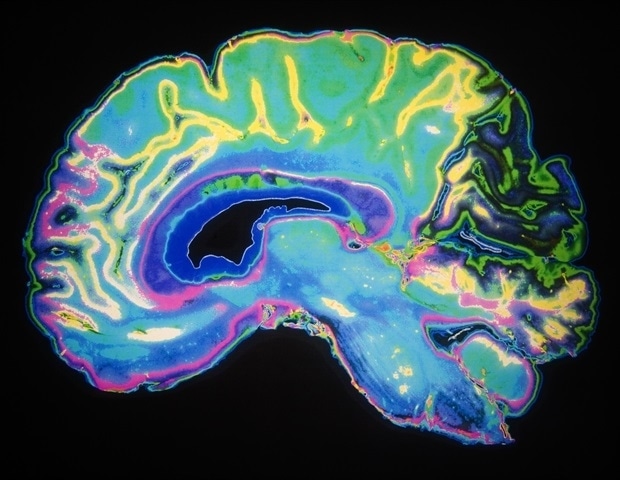

Μια ομάδα ερευνητών από το Ινστιτούτο Νευροεπιστημών (ΙΝ), το οποίο είναι κοινό κέντρο του Ισπανικού Εθνικού Συμβουλίου Έρευνας (CSIC) και του Πανεπιστημίου Μιγκέλ Ερνάντες στην Ελτσε, εντόπισε έναν εγκεφαλικό κύκλωμα που είναι κρίσιμο για τη χωρική μνήμη. Στη μελέτη τους, που δημοσιεύθηκε στο Cell Reports, περιγράφεται για πρώτη φορά η σύνδεση μεταξύ των δύο ημισφαιρίων του ιππόκαμπου, όπου νευρώνες στην περιοχή CA1 του δεξιού ημισφαιρίου στέλνουν προεκτάσεις στο αριστερό ημισφαίριο, ειδικότερα στο σούμπικουλο. Τα ευρήματα δείχνουν ότι αυτή η επικοινωνία είναι απαραίτητη για την πλοήγηση και τη διατήρηση τοποθεσιών. Επιπλέον, η μελέτη αποκαλύπτει ότι αυτό το κύκλωμα αλλοιώνεται σε ποντίκια με γενετική μετάλλαξη σχετιζόμενη με τη σχιζοφρένεια.

Ο εγκέφαλος χωρίζεται σε δύο ημισφαίρια που επεξεργάζονται πληροφορίες με εν μέρει εξειδικευμένο τρόπο, αλλά απαιτούν συνεχώς συντονισμό μεταξύ τους. Ωστόσο, οι συγκεκριμένες συνδέσεις που διευκολύνουν αυτή την επικοινωνία σε περιοχές που σχετίζονται με τη μνήμη, όπως ο ιππόκαμπος, είναι σε μεγάλο βαθμό άγνωστες. Η ομάδα αναγνώρισε μία από αυτές τις συνδέσεις: μια προ projection που συνδέει την περιοχή CA1 του δεξιού ημισφαιρίου με το σούμπικουλο του αριστερού ημισφαιρίου. Η έρευνα χρησιμοποίησε τεχνικές παρακολούθησης νευρώνων που επιτρέπουν την παρακολούθηση των συνδέσεων μεταξύ των νευρώνων.